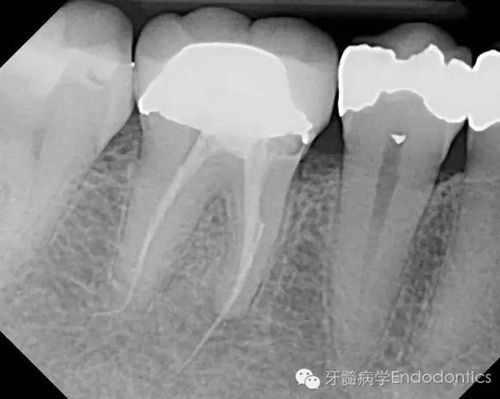

患者因右下第一前磨牙劇烈疼痛、腫脹來診,自訴2年前該牙行根管治療,突發(fā)劇痛。X線示患牙已行根管治療并超填?;佳涝\斷為已行根管治療合并急性根尖周膿腫。一些牙醫(yī)和牙髓病專科可能會直接采取根尖手術(shù)治療患牙,而我認(rèn)為手術(shù)是最終手段,尤其對于該病例。

圖2.術(shù)前X線片(b)